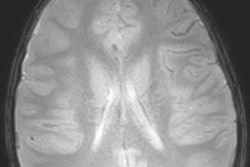

The institutions are the first commercial customers for Nociscan, which analyzes MR spectroscopy images to detect chemical biomarkers associated with disk pain and the structural integrity of the annulus of the disk. The software is designed to serve as an adjunctive tool for diagnosis of degenerative disk disease pain, according to the vendor. It was developed initially at the University of California, San Francisco.